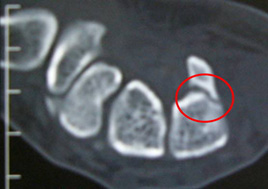

手のひら側のCT画像ですが、突起=鉤が骨折しているのが確認できます。

有鈎骨の骨折により、ギヨン管症候群を発症します。